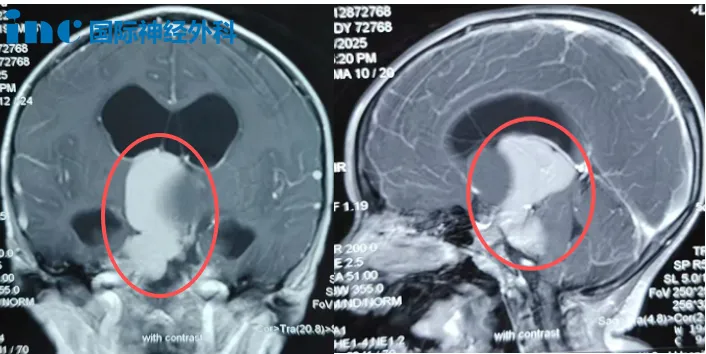

術(shù)前MRI,小安腦中的“大蟲子”

這條“蟲”潛伏在小安的顱內(nèi),引發(fā)持續(xù)頭痛、嘔吐,導(dǎo)致發(fā)育遲滯和四肢無(wú)力。影像檢查顯示,腫瘤從鞍上延伸至第三腦室和橋小腦角區(qū),并已引發(fā)腦積水。隨著“蟲子”向“生命禁區(qū)”腦干生長(zhǎng),小安的癥狀日益加重:嘔吐變得劇烈,頭痛持續(xù)不斷,右腿活動(dòng)也逐漸不靈,走路時(shí)常絆倒。